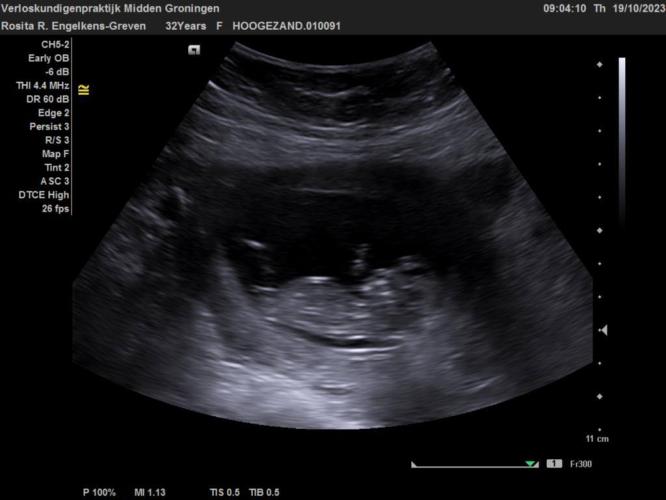

Vandaag de tweede echo gehad en wat was dat toch weer een bijzonder moment.

Hij/Zij zwaaide ook nog even zo leuk naar ons en we hebben eindelijk het hartje gehoord.

Mijn uitgerekende datum is vandaag nu toch echt vastgesteld op 3 Mei 2024

In december hebben wij de 20 weken echo en dan krijgen wij ook te horen wat het gaat worden.

Nou dit was voor nu eerst even weer een update en ik hoop dat jullie er van genieten om deze mooie echo foto nog even weer te zien :)